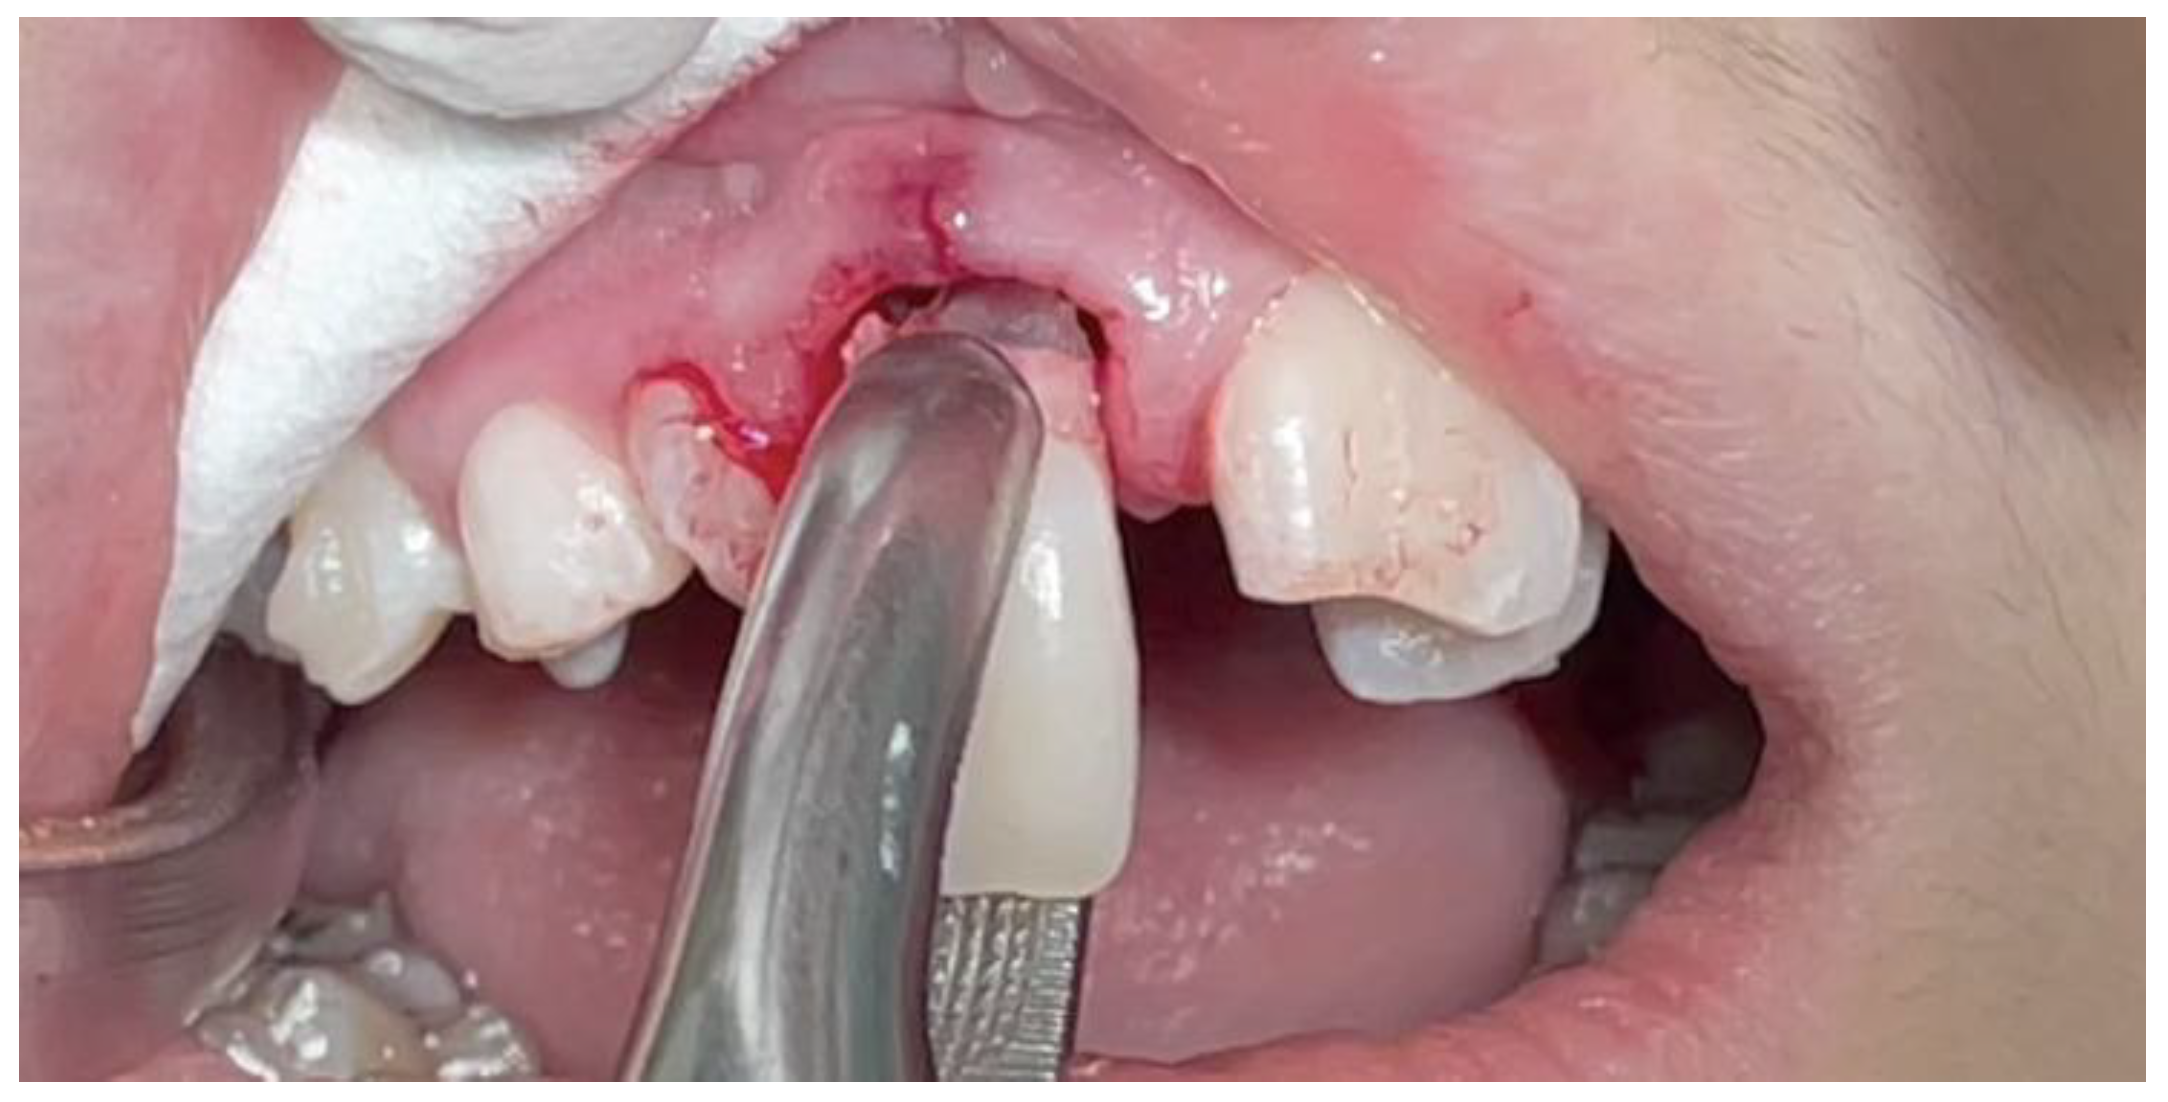

| Pinho T., Amaral R. 2025 | ♀ 13 YO | Mx.C.I1 | C | R | V (impacted) | Cl I | Maintained | -Total root resorption of tooth #11 due to the position of the ectopic canine |

3.2. Clinical Case